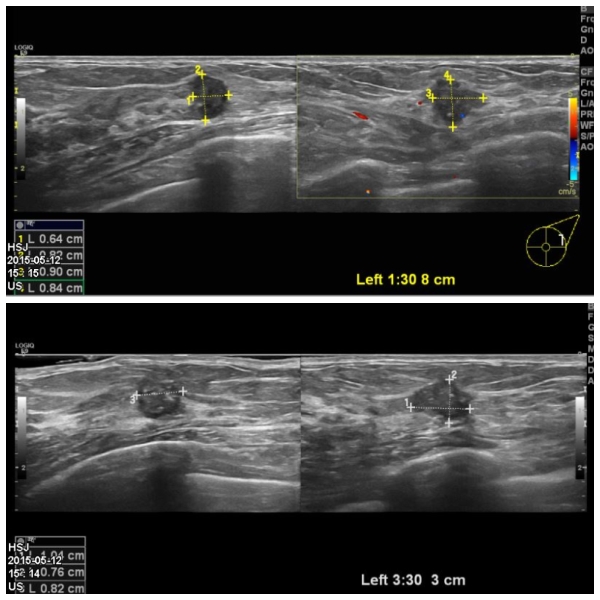

좌측 유방에 만저지는 몽우리로 내원하신 40대 여성 분으로  좌측 1 :30 분에서 8cm

떨어진 거리의 혹과, 3 :30분에서 3cm 떨어진 거리의 혹을 조직검사 하였으며

두 혹다 침윤성 유관암 진단 되었습니다.